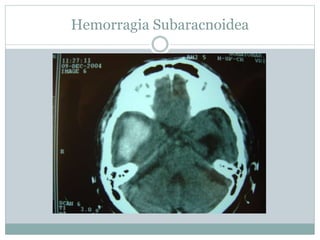

Hemorragia Subaracnoidea